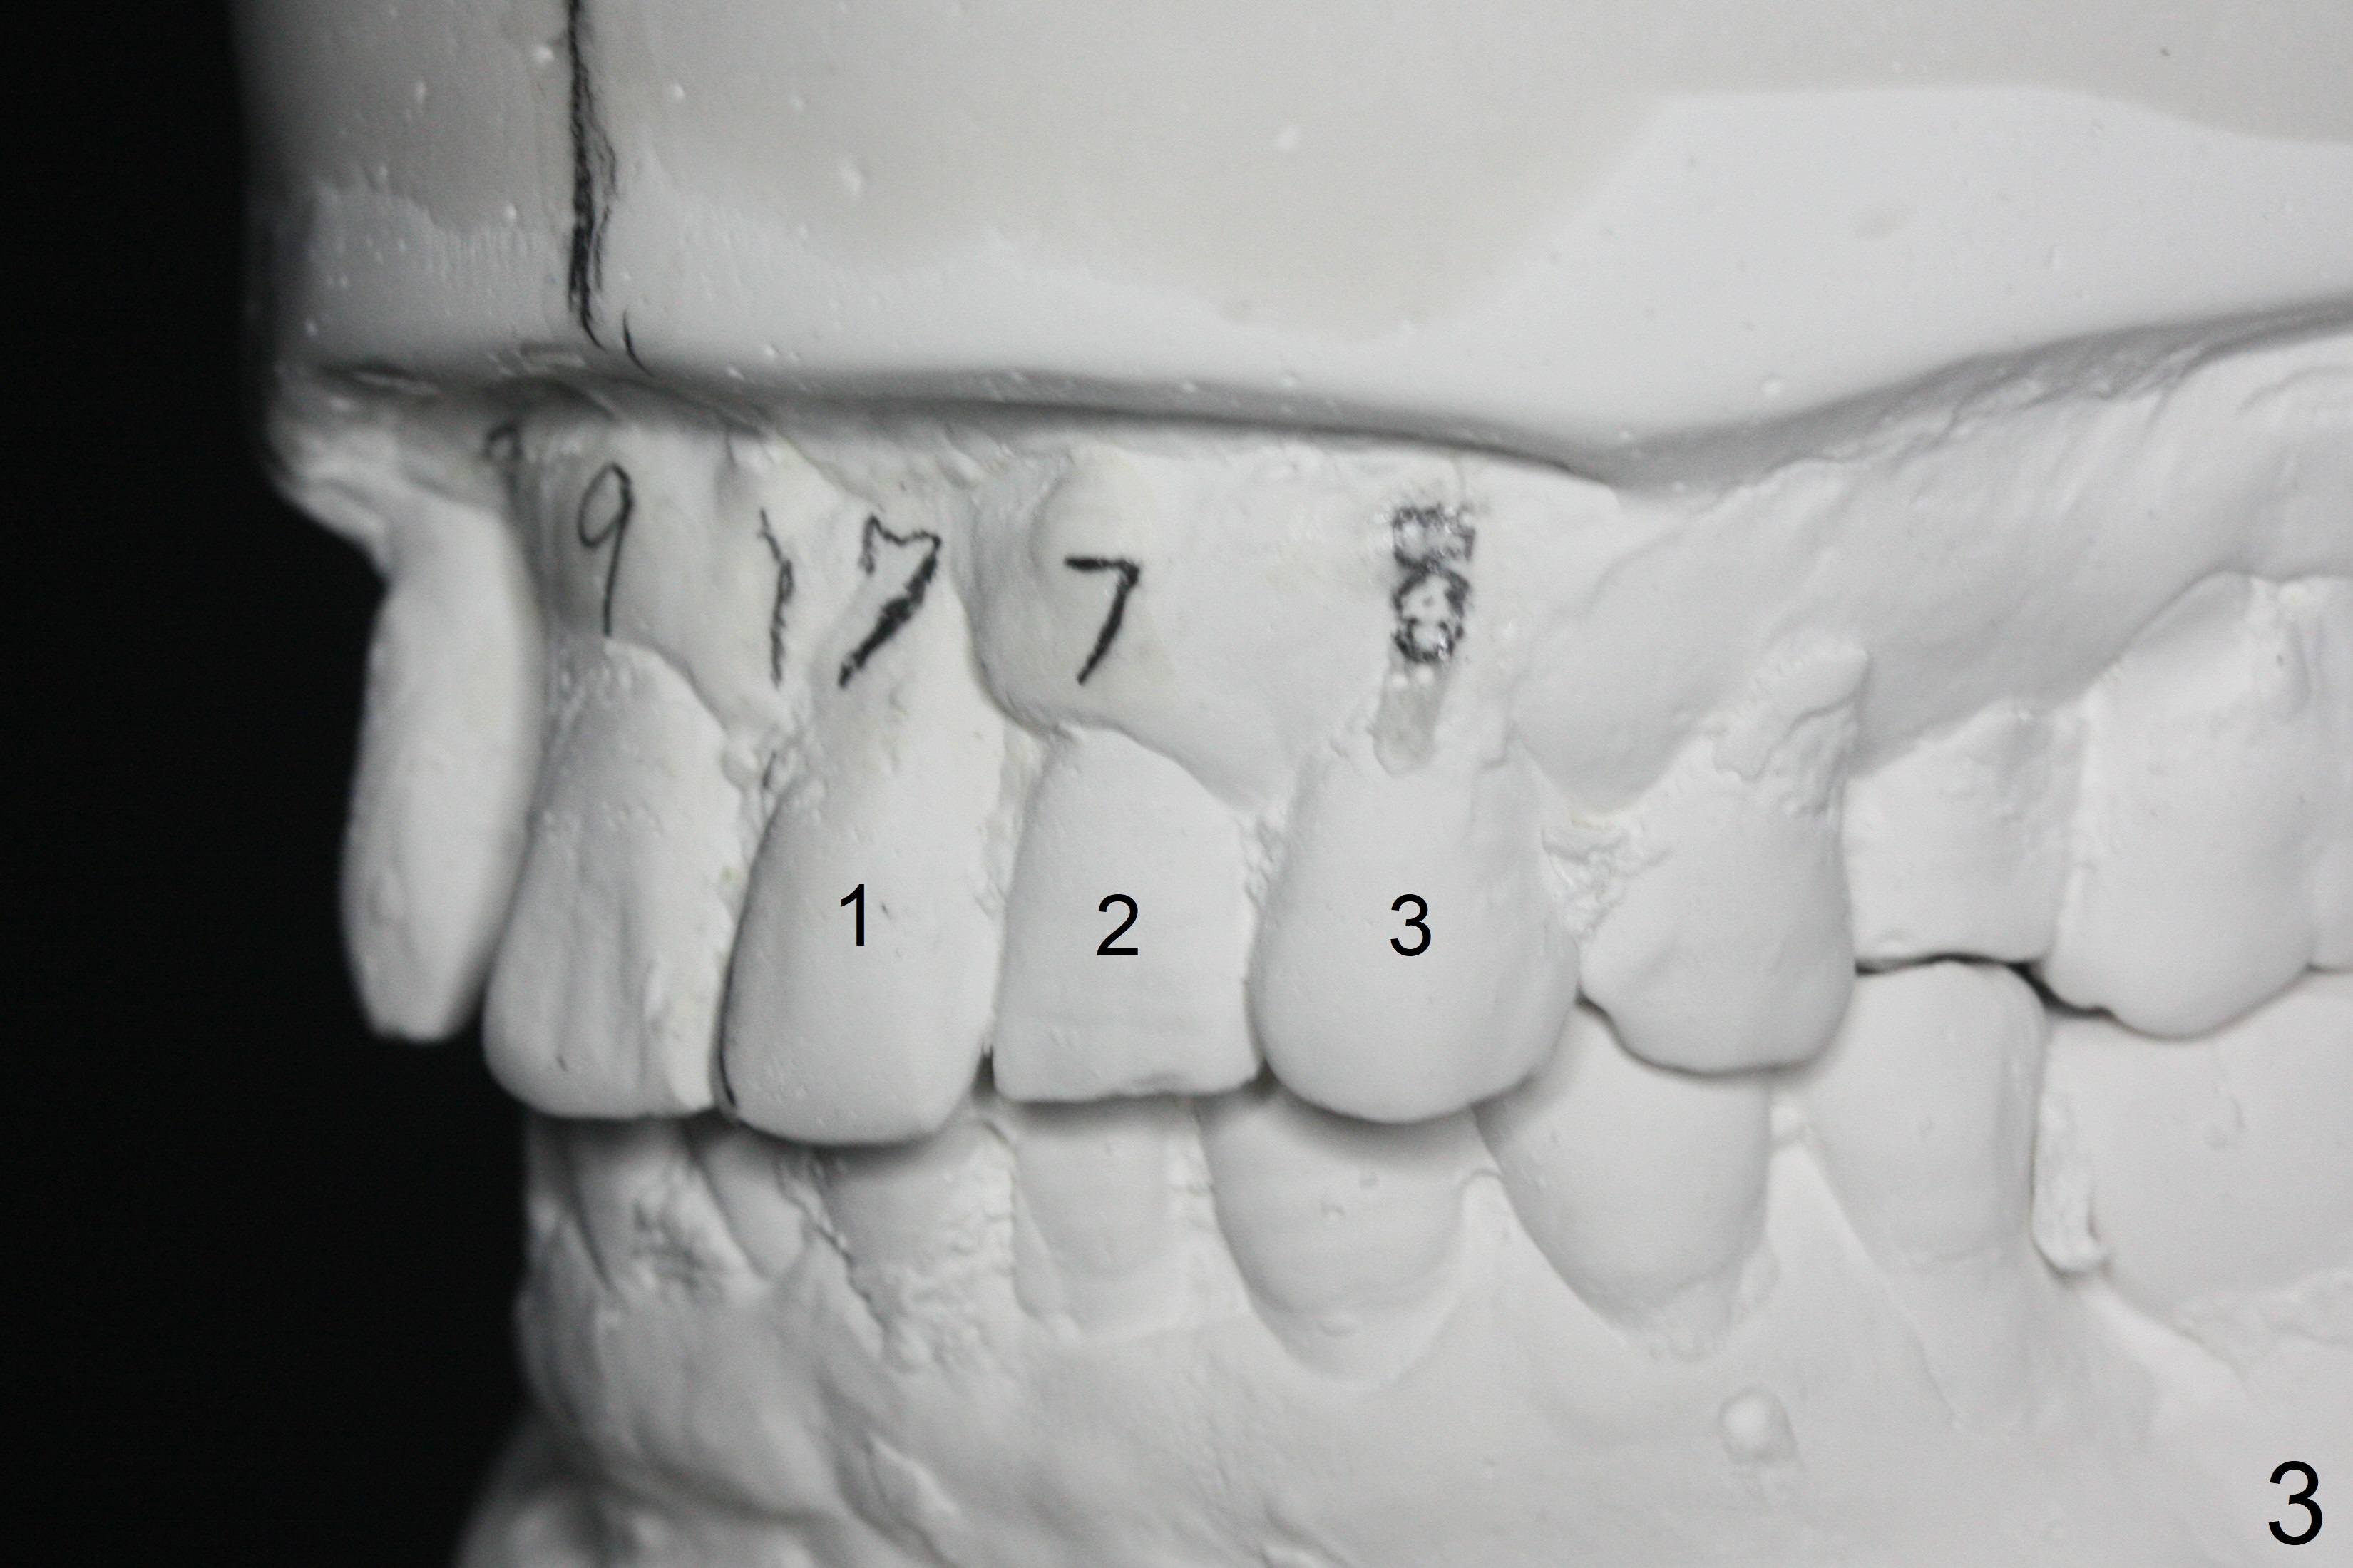

In spite of several warnings against orthodontic treatment for a 47-year-old man with chronic periodontitis, he requests it once more time before UL1 implant restoration. How to correct UR2 cross bite (Fig.1-4)? The number in pencil represents the width of each tooth in mm. For example the width of UR1 is 9 mm, whereas that of UL1 is 7 mm (Fig.2). The pencil line represents the facial midline and the upper dental midline. Ideally the UL1 should be moved distally ~ 1 mm.